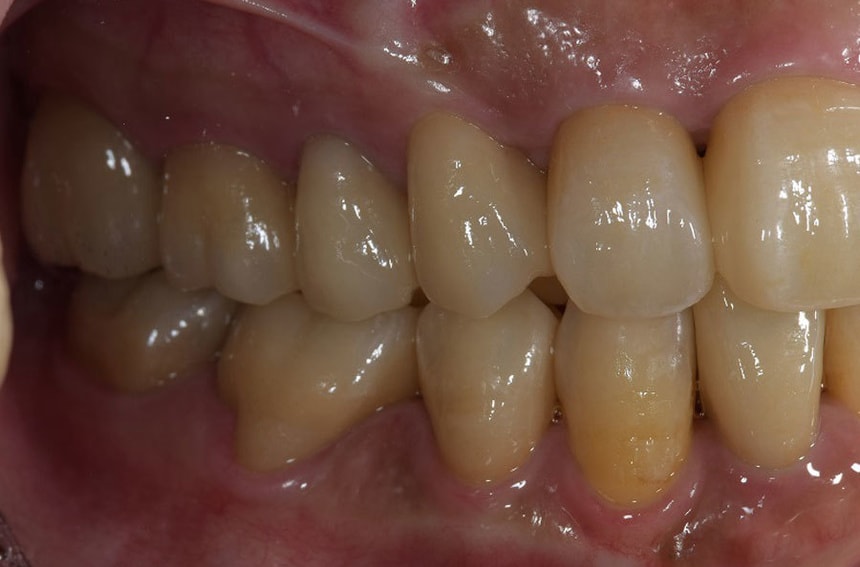

左奥歯の治療前後

奥歯をインプラントにて治療し、よく噛めるようにしました。また、虫歯や歯の根の治療のやり直しを行いセラミックにて審美的に修復しました。

どんな治療にもメリット・デメリットがあります。患者さんの年齢や口腔内の状態、さまざまな要因で、治療のメリット・デメリットの大きさは、変わってきます。患者さんの状態によって、受ける治療のメリット・デメリットは異なるので、治療を受ける際は、よく説明を受けられてからの方が、安心して治療を受けることが出来るかなと思います。

インプラントや入れ歯、ブリッジもそれぞれメリット・デメリットがあります。

なかなか難しいのですが、それぞれの患者さんに、ベストの治療法が提案できればなと思います。